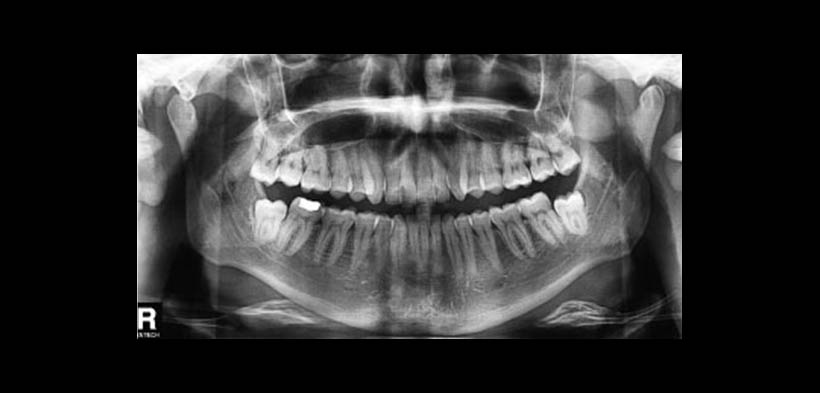

Fig. 2. Radiografía panorámica.